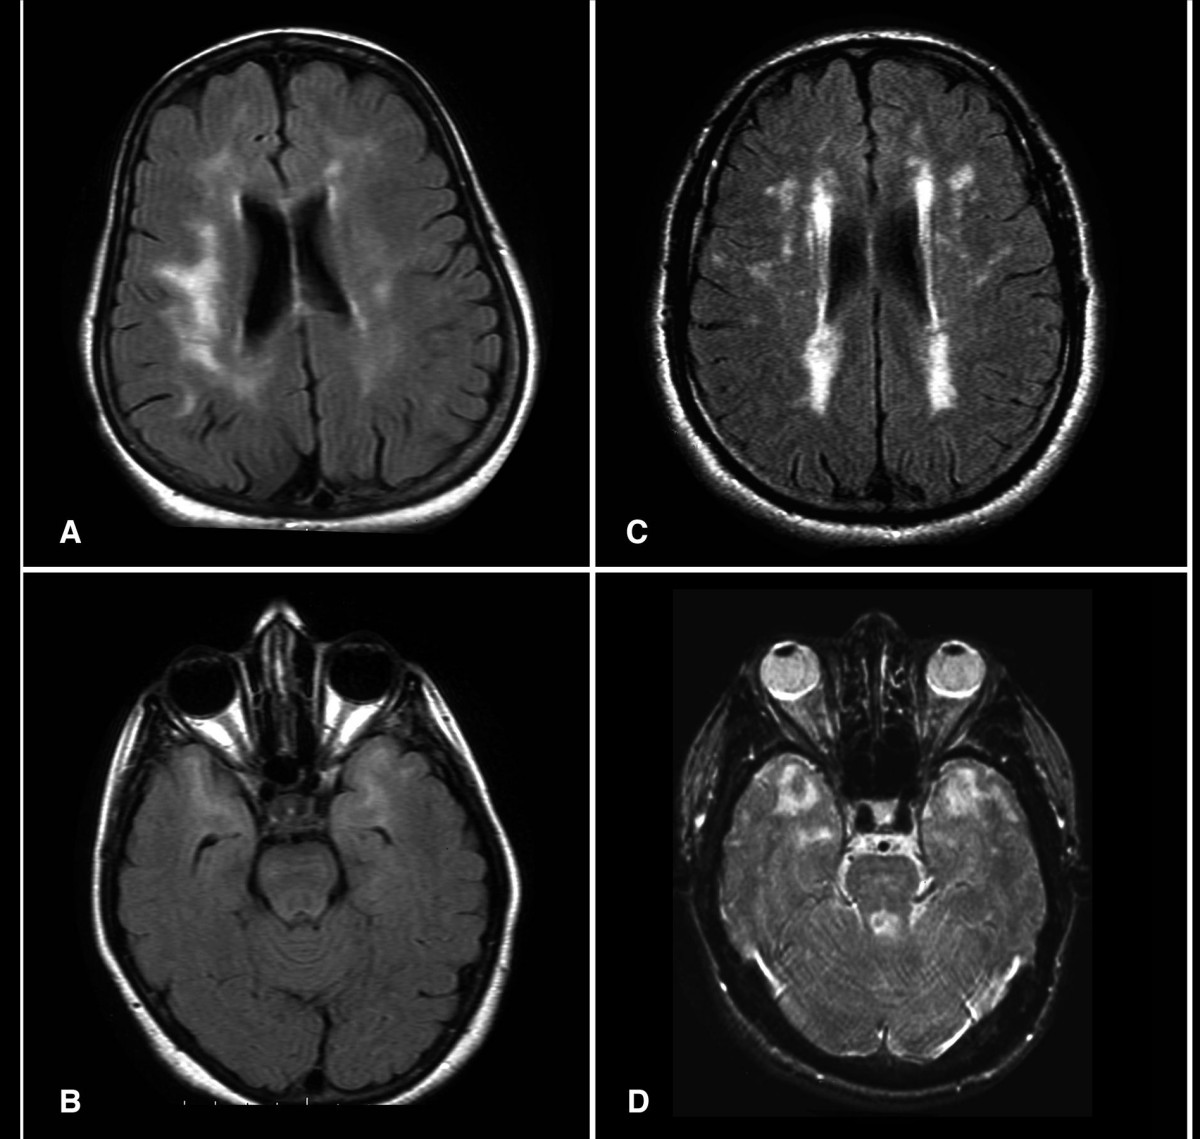

- CADASIL (Cerebral Autosomal Dominant Arteriopathy with Subcortical Infarcts and Leukoencephalopathy): 19번 염색체에 위치한 ''NOTCH3'' 유전자의 돌연변이로 인해 발생하는 유전 질환이다.[84] ''NOTCH3'' 유전자는 세포막을 관통하는 막관통 단백질을 만드는 역할을 하는데, 그 기능은 아직 명확히 밝혀지지 않았다. 유전자 돌연변이가 생기면 이 단백질이 작은 혈관과 중간 크기 혈관의 벽에 쌓이게 된다.[84] 이 질환은 주로 초기 성인기에 편두통, 뇌졸중, 기분 장애, 인지 기능 저하 등의 증상으로 나타난다. MRI 검사를 통해 뇌의 백질 변화와 반복적인 뇌졸중의 흔적을 확인할 수 있으며, 유전자 검사를 통해 최종적으로 진단한다.[85]

자기공명영상( 核磁気共鳴画像法|가쿠지키 쿄메이 가조호jpn, MRI)는 CT보다 더 이른 시기에 뇌경색 병변을 발견할 수 있다.

- T2 강조 영상(T2WI): 발병 약 6시간 후부터 병변 부위가 고신호(밝게 보임)로 나타난다. 이는 세포( 細胞|사이보jpn )의 부종을 반영한다.

- 확산강조영상(DWI): 발병 약 3시간 후부터 병변 부위가 고신호로 나타나 DWI가 가장 초기에 뇌경색을 진단하는 데 유용하다. 이론적으로 DWI에서 고신호를 보이는 부위는 이미 비가역적인 손상을 입은 것으로 간주하며, 그 주변에는 아직 회복 가능한 영역인 페넘브라( ペナンブラ|페난부라jpn )가 존재한다고 본다. 하지만 DWI 고신호 영역 대부분이 실제 괴사 부위와 일치하지만, 일부 희미한 병변 속에는 회복 가능한 조직이 포함될 수도 있다. 반대로, 발병 극초기에는 DWI에서도 병변이 나타나지 않는 위음성(false negative) 경우가 있다. 발병 24시간 이내에도 약 5%의 위음성이 보고되며, 특히 발병 6시간 이내의 척추동맥 관류 영역에서는 위음성률이 20%에 달하며, 연수 병변에서 흔하다. 대뇌피질 병변의 위음성률은 약 2%로 낮다. 따라서 첫 DWI 검사에서 이상 소견이 없더라도 임상 증상으로 뇌경색이 강력히 의심되면 24시간 후에 재촬영하는 것이 권장된다. 이때는 3mm 정도의 얇은 절편 두께와 높은 b 값(2000 이상)으로 촬영하면 검출률을 높일 수 있다.

- 초급성기: 세포성 부종으로 인해 물 분자의 확산이 제한되어 확산 계수가 낮아진다. 이는 DWI에서 고신호, ADC-MAP에서 저신호로 나타난다.

- 급성기: 모세혈관의 혈액뇌장벽(BBB)이 손상되어 혈관성 부종이 발생한다. 이로 인해 조직 내 수분 함량이 증가하여 T2WI에서 고신호로 보인다. 급성기에 혈류가 재개통되면 혈관성 부종이 악화되어 심한 뇌부종( 脳浮腫|노후슈jpn )이나 출혈성 뇌경색( 出血性梗塞|슛케쓰세이 코소쿠jpn )이 발생할 수도 있다.

- 아급성기: 세포가 괴사하고 혈관이 손상되면서 확산 계수가 다시 증가하여 일시적으로 정상처럼 보이는 현상(pseudo-normalization)이 나타날 수 있다. DWI는 T2 강조 영상의 영향(T2 shine through)으로 아급성기 후반까지 고신호가 지속될 수 있다. 따라서 DWI 고신호만으로 확산 계수 저하나 초급성기 뇌경색으로 단정할 수 없으므로 ADC-MAP과 함께 평가해야 한다. 발병 약 2주경에는 CT에서도 혈관성 부종이 감소하면서 병변이 주변 조직과 비슷한 밀도로 보여 일시적으로 잘 보이지 않게 되는데, 이를 포깅 효과(fogging effect, FE)라고 한다. 아급성기에는 연막-뇌막 문합을 통한 측부 혈행로나 보상적인 혈류 증가로 인해 비교적 작은 괴사 부위 내에 미세 출혈이 관찰될 수 있으며, 이는 T2* 강조 영상에서 저신호로 나타난다. 이러한 출혈은 급성기의 출혈성 뇌경색과 달리 심각한 신경학적 증상 악화를 유발하지는 않지만, 소뇌 뇌경색에서 이러한 소견이 보일 경우 항혈소판제 투여를 신중히 고려해야 한다.

- 만성기: 괴사된 조직이 흡수되고 흉터 조직으로 대체되면서 T2WI에서 고신호 소견을 보인다. 조직 결손 정도에 따라 FLAIR 영상에서는 세포외액 공간 확대로 인해 저신호로 보일 수도 있다.